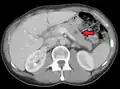

CT image of multiple liver metastases -

CT image of a lung metastasis -